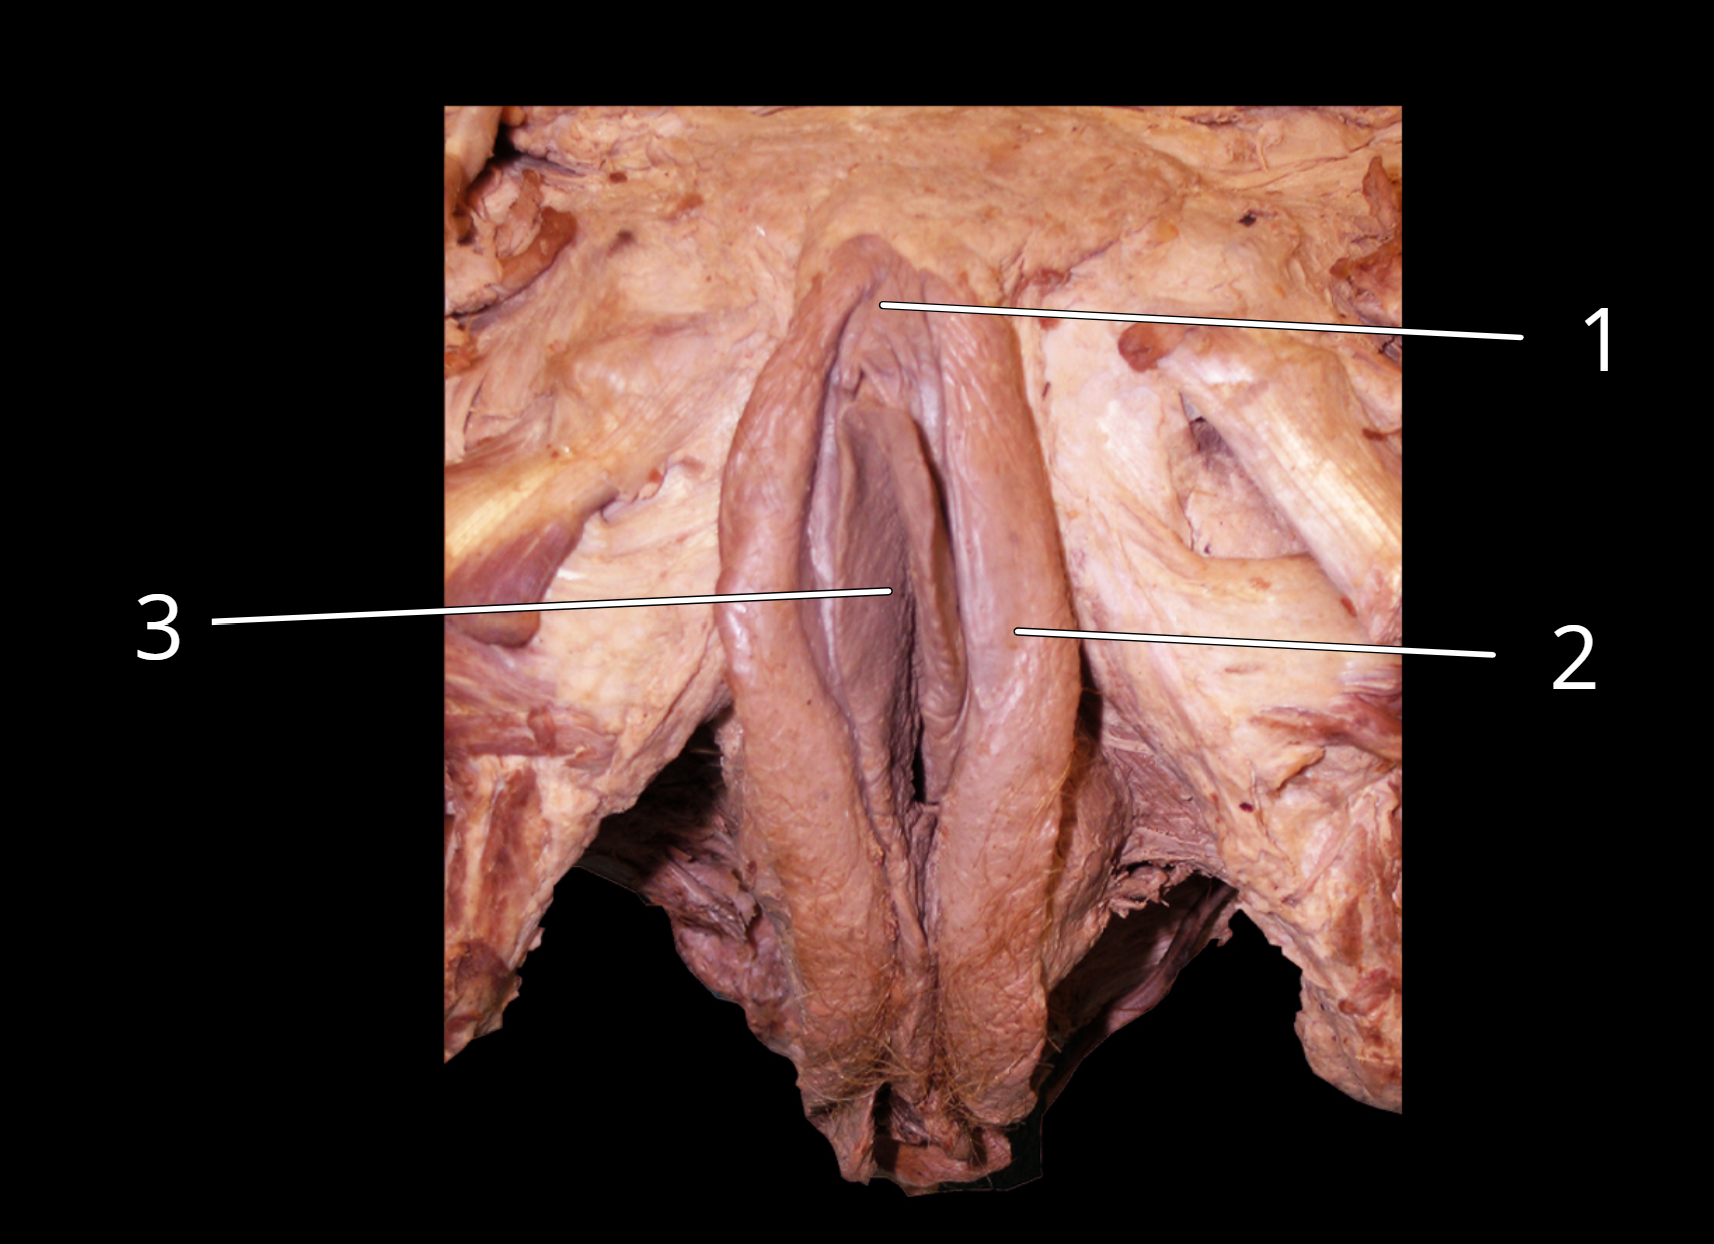

Female external genitalia

1. Clitoris

2. Labia majora

3. Labia minora